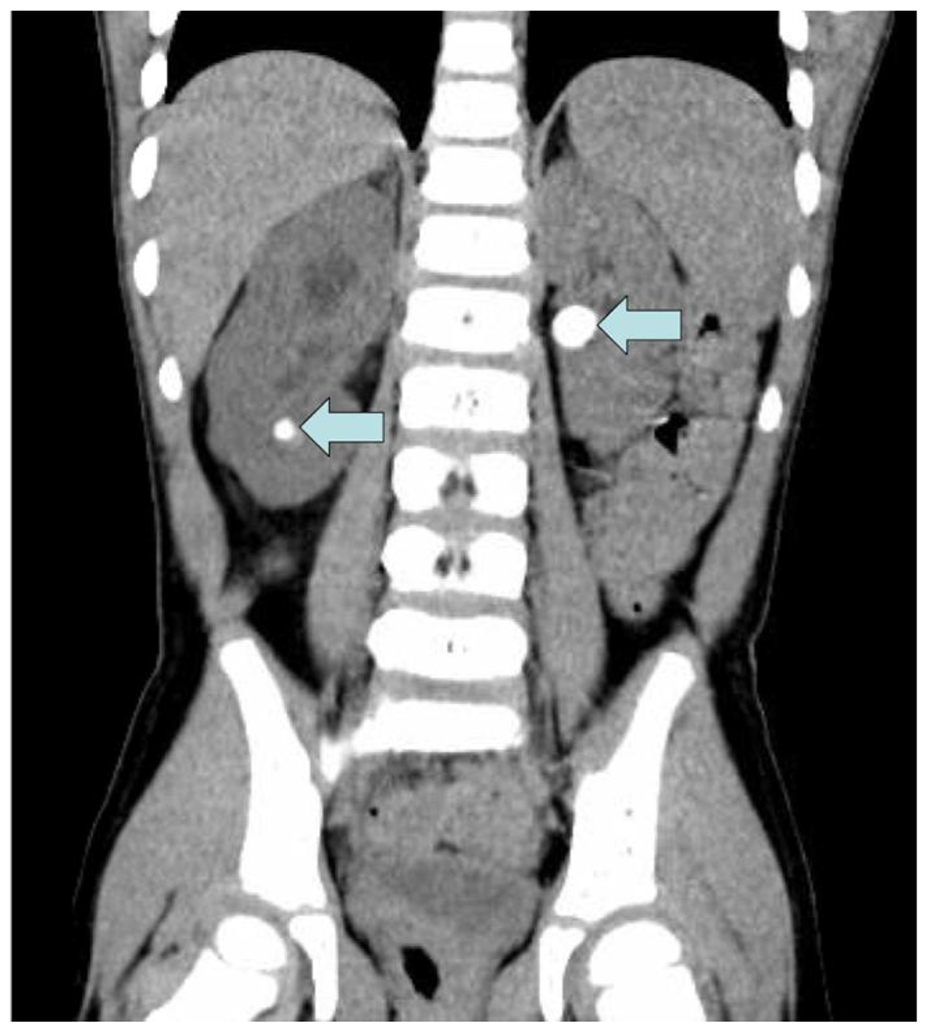

A 3-year-old boy previously diagnosed with Lesch-Nyhan disease presented with abdominal pain, nausea, and vomiting in September 2014. He had a similar presentation to the hospital 3 months prior and was noted to have right hydroureteronephrosis on renal sonogram at that time, which persisted on repeat sonogram. No urolithiasis was noted on sonogram. He underwent an abdominal/pelvic CT scan which revealed an obstructing stone in his right ureter of 7 mm (Fig. 1) and a large left renal pelvis stone of about 1 cm (Fig. 2). His renal function was elevated with a Cr of 0.7 mg/dL (0.4 - 0.7 mg/dL) and his eGFR was 59.9 mL/min/1.73 m2 calculated using the Schwarz equation. He was currently on treatment with allopurinol and his serum uric acid was 3.7 mg/dL (2.1 - 5.6 mg/dL) and his urinary uric acid level was 8.8 mg/dL (9.0 - 114 mg/dL). Urine pH was 7.0. The patient underwent cystourethroscopy and bilateral lithotripsy along with bilateral ureteral stent placement. Stone analysis revealed 100% xanthine stones. The patient was discharged and sent home from this encounter but has since presented twice with obstructing xanthine stones that have required intervention over the past several years.

![]() Click for large image | Figure 2. Left renal pelvis and right lower pole stones on CT. |